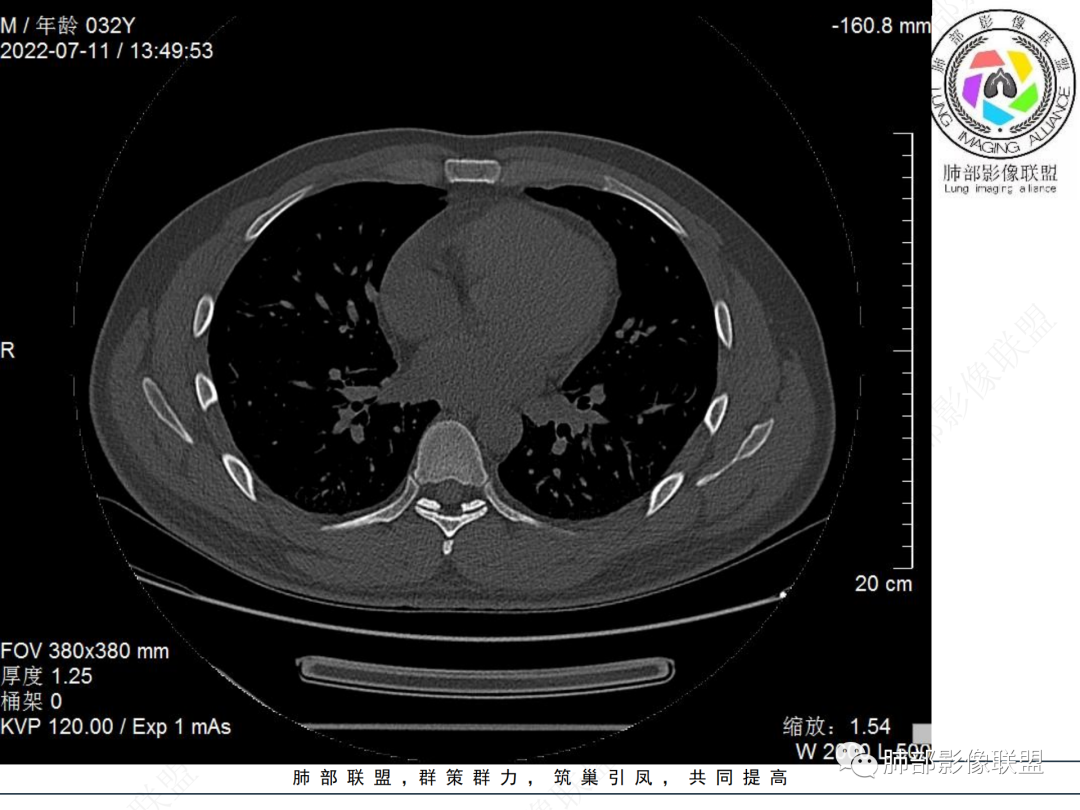

左肺下叶后基底段开口处结节,边缘光滑清楚,没有增强扫描,年轻男性患者痰血三天,考虑1.良性病变:腺瘤、错构瘤、平滑肌瘤

2.恶性:类癌、粘液表皮样癌。

左肺下叶外后基底段气管内见结节状影,边缘部分清晰。考虑错构瘤,待排恶性病变。

左肺下叶气管内外占位病变,咯血病史,考虑类癌,粘表待排。

青年男性,左肺下叶后基底段支气管开口软组织结节,边缘光整,气管镜提示质软,易出血,考虑类癌

左肺下叶后基底段开口处结节,边缘光滑清楚,年轻患者考虑鳞癌或腺样囊腺癌

左肺下叶气道腔内占位,远端无花花草草,疾病谱:鳞,类癌,粘表,腺样囊腺癌,小,无增强,不好判断,临床咯血,选类癌。

大支气管腔内结节,考虑类癌

左肺下叶后基底段开口处结节影,边缘光滑,患者年龄较小,首选类癌

男性,咳血左肺下叶支气管腔内结节影,没有阻塞性炎症,考虑类癌,鳞癌

年轻男性,支气管内结节,首先类癌

左肺下叶后基底段开口处腔内见壁结节,花生米样,宽基底,补充增强及矢状位重建,确定我无向壁外突破浸润生长,另见强化的特点,临床触之易出血,类Ca可能性大。

年轻男性,支气管腔内占位,边缘尚平整,年轻人,首先类癌,鉴别错构

年轻男性,咳血,左肺下叶后基底段支气管腔内结节,边缘光滑,首先考虑青年三件套,类癌大于粘液表皮样癌,支气管镜质软,触之易出血,鉴别血管瘤,平滑肌瘤

左肺下叶后基底段开口部结节,密度较均匀一致,边缘较光整,目测密度偏低,支气管镜示:质软、触之易出血,考虑恶性,类癌。

支气管腔内结节,有蒂与支气管壁连接,考虑良性病变可能性大,支气管错构瘤 血管瘤一类的

左肺下叶后基底段支气管腔内结节,有蒂,容易出血,先考虑良性病变,肉芽组织型血管瘤,与类癌鉴别。

青年男性,左肺下叶后基底段支气管开口软组织结节,边缘光整,气管镜提示质软,易出血,考虑恶性类癌

左肺下叶后基底段开口处结节影,边缘光整,年轻患者,伴咯血,考虑鳞癌,类癌不能排除